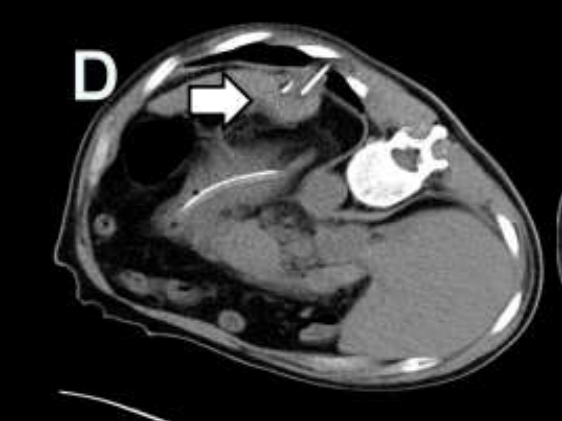

術(shù)中通過CT定位,聯(lián)合彩色超聲引導(dǎo)穿刺,分別經(jīng)腹,經(jīng)左側(cè)胸壁進(jìn)針。2支消融針間隔2.5cm且互相平行,消融針針尖暴露2cm,開始進(jìn)行消融。因肝臟腫瘤體積較大,對(duì)腫瘤分區(qū)進(jìn)行多次消融,確保消融范圍能完全覆蓋。

術(shù)中操作

復(fù)查結(jié)果

術(shù)后1周和術(shù)后2月復(fù)查腹部CT均提示:肝臟及左側(cè)腹膜腫瘤可見大片狀低密度壞死區(qū),肝臟腫瘤外周有少許強(qiáng)化灶。心電圖及心肌酶未見明顯異常,腫瘤標(biāo)志物指標(biāo)顯著下降?;颊叩捏w重較術(shù)前上升4kg,疼痛程度及日?;顒?dòng)能力較前明顯改善。

術(shù)后復(fù)查:左為術(shù)后1周,右為術(shù)后2月